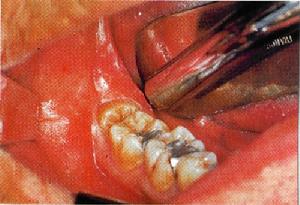

7、咬合板治療:製作一個牙墊,晚上睡前戴在牙頜上,早晨取下,緩解肌肉緊張。目前最容易被醫師和患者接受,防止牙磨損效果明顯但並不能治療磨牙症。